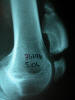

Densitometría en calcáneo